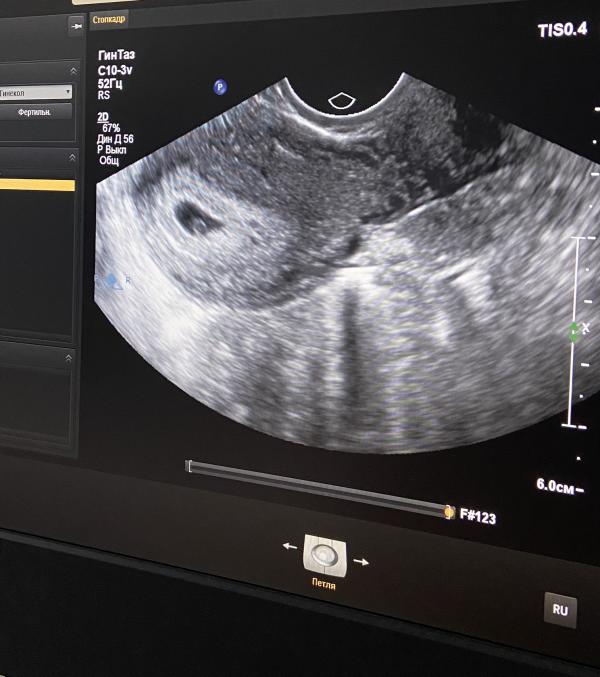

Пя 17мм, жм 2.1,эмбрион должен начать визуализироваться на днях

Сказали выделений не пугаться , по узи все отлично